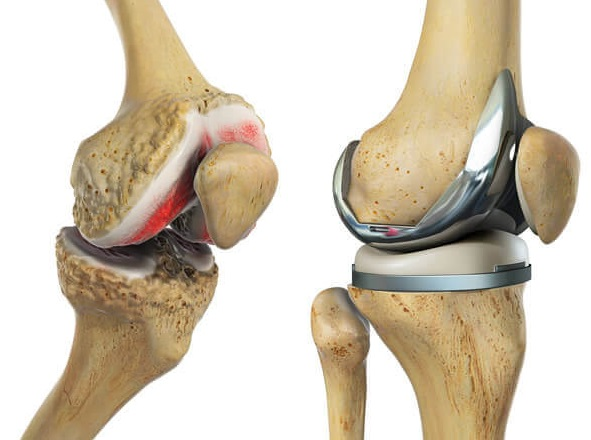

Proteza totale e gjurit (Total Knee Replacement) është një ndërhyrje kirurgjikale ku sipërfaqet e dëmtuara të nyjës së gjurit zëvendësohen me implante artificiale (metal, plastikë të fortë ose qeramikë). Kjo procedurë përdoret zakonisht kur dëmtimet janë të rënda dhe trajtimet konservative nuk japin rezultat.

- Kirurgu heq sipërfaqet e dëmtuara të kockave: fundin e femurit, pjesën e sipërme të tibias dhe ndonjëherë pjesën e patelës.

- Vendosen komponentët metalikë dhe plastikë që krijojnë një artikulacion të ri.